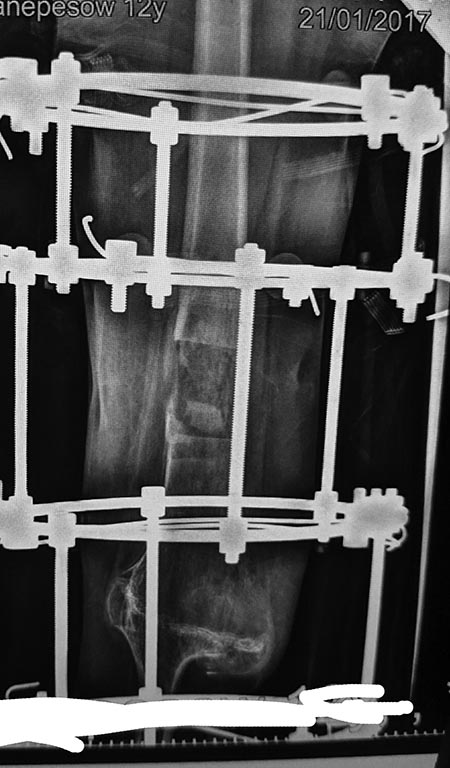

[Ortho] Невыносимая боль на аппарате Илизарова

Снимки

Имя     : R1.JPG

Имя     : R2.jpg